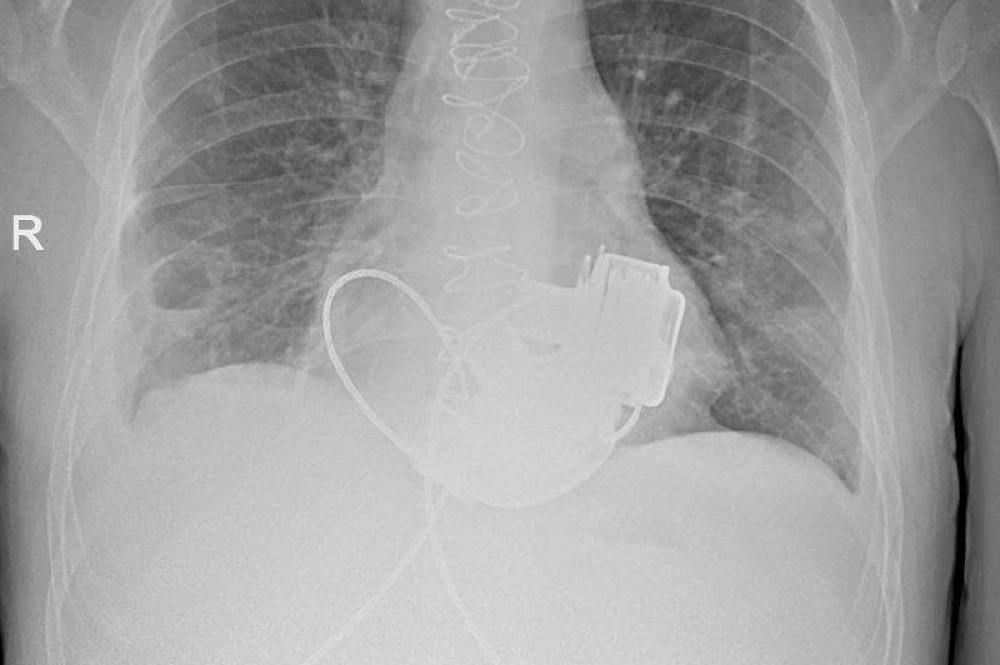

В Мариинской больнице завершается лечение пациента, которого сами врачи называют уникальным. В конце ноября 2025 года 36-летнему петербуржцу Антону Павлову впервые в стране имплантировали сразу два искусственных желудочка — левый и правый (LVAD и RVAD). Это решение спасло ему жизнь: без операции мужчина погиб бы в считаные дни.

После операции Антон Павлов стал единственным в России человеком, живущим без пульса. Искусственные желудочки создают ламинарный, а не пульсирующий кровоток, поэтому привычно измерить давление тонометром или нащупать пульс теперь невозможно.